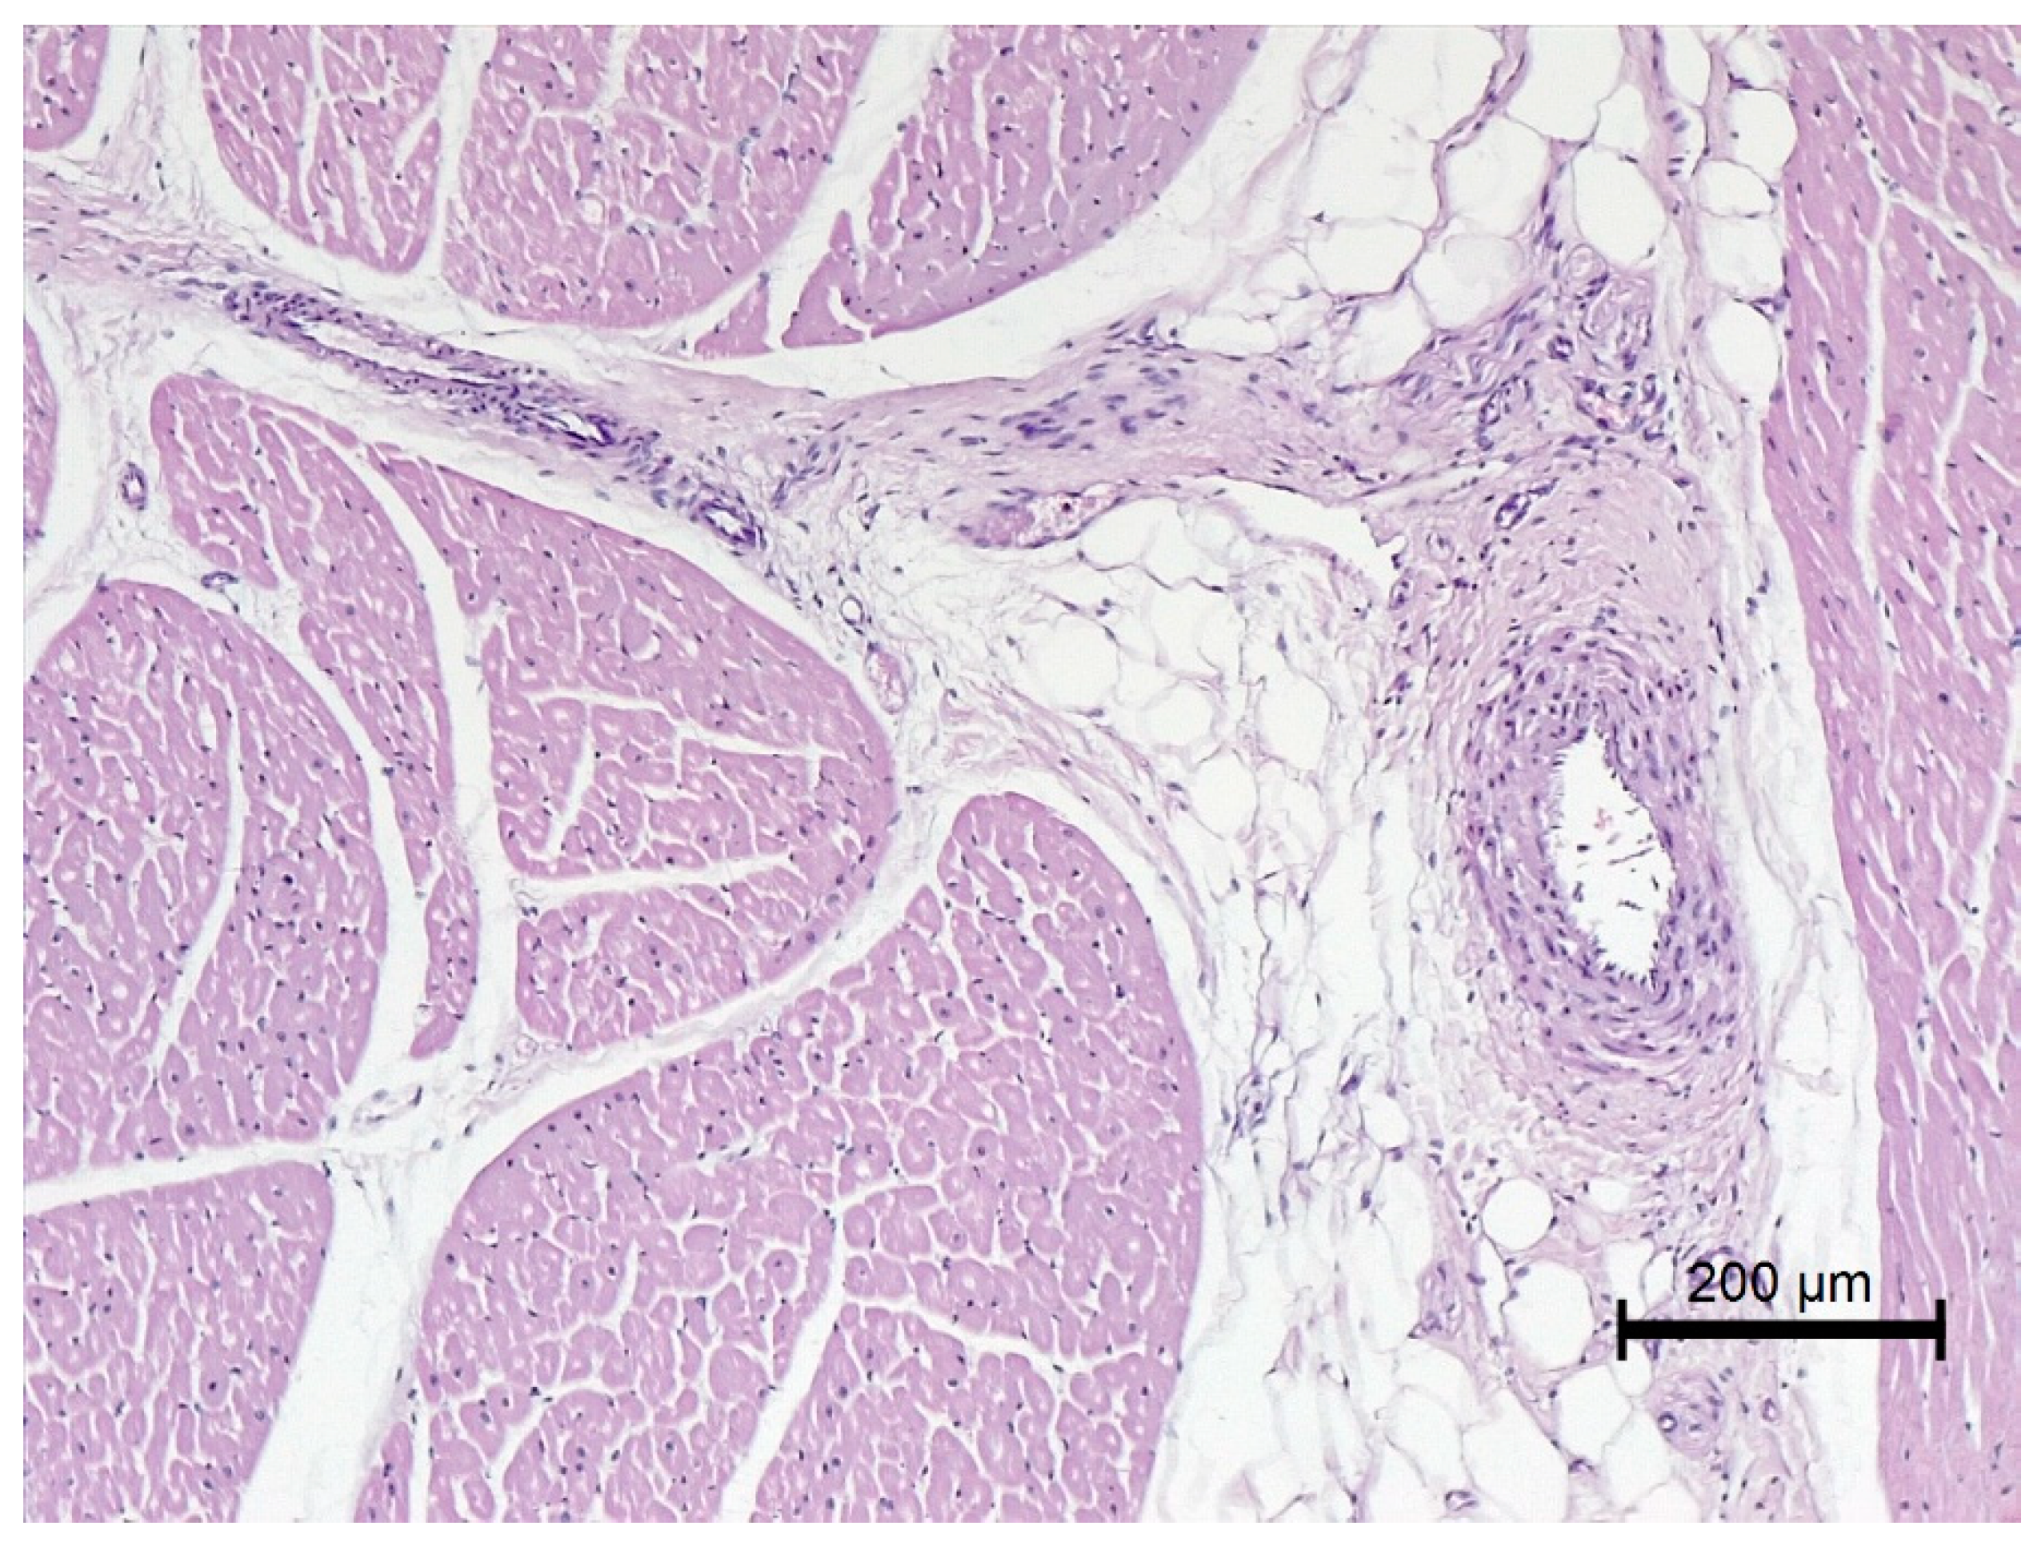

2.2.1. Anatomical and Histological Analysis